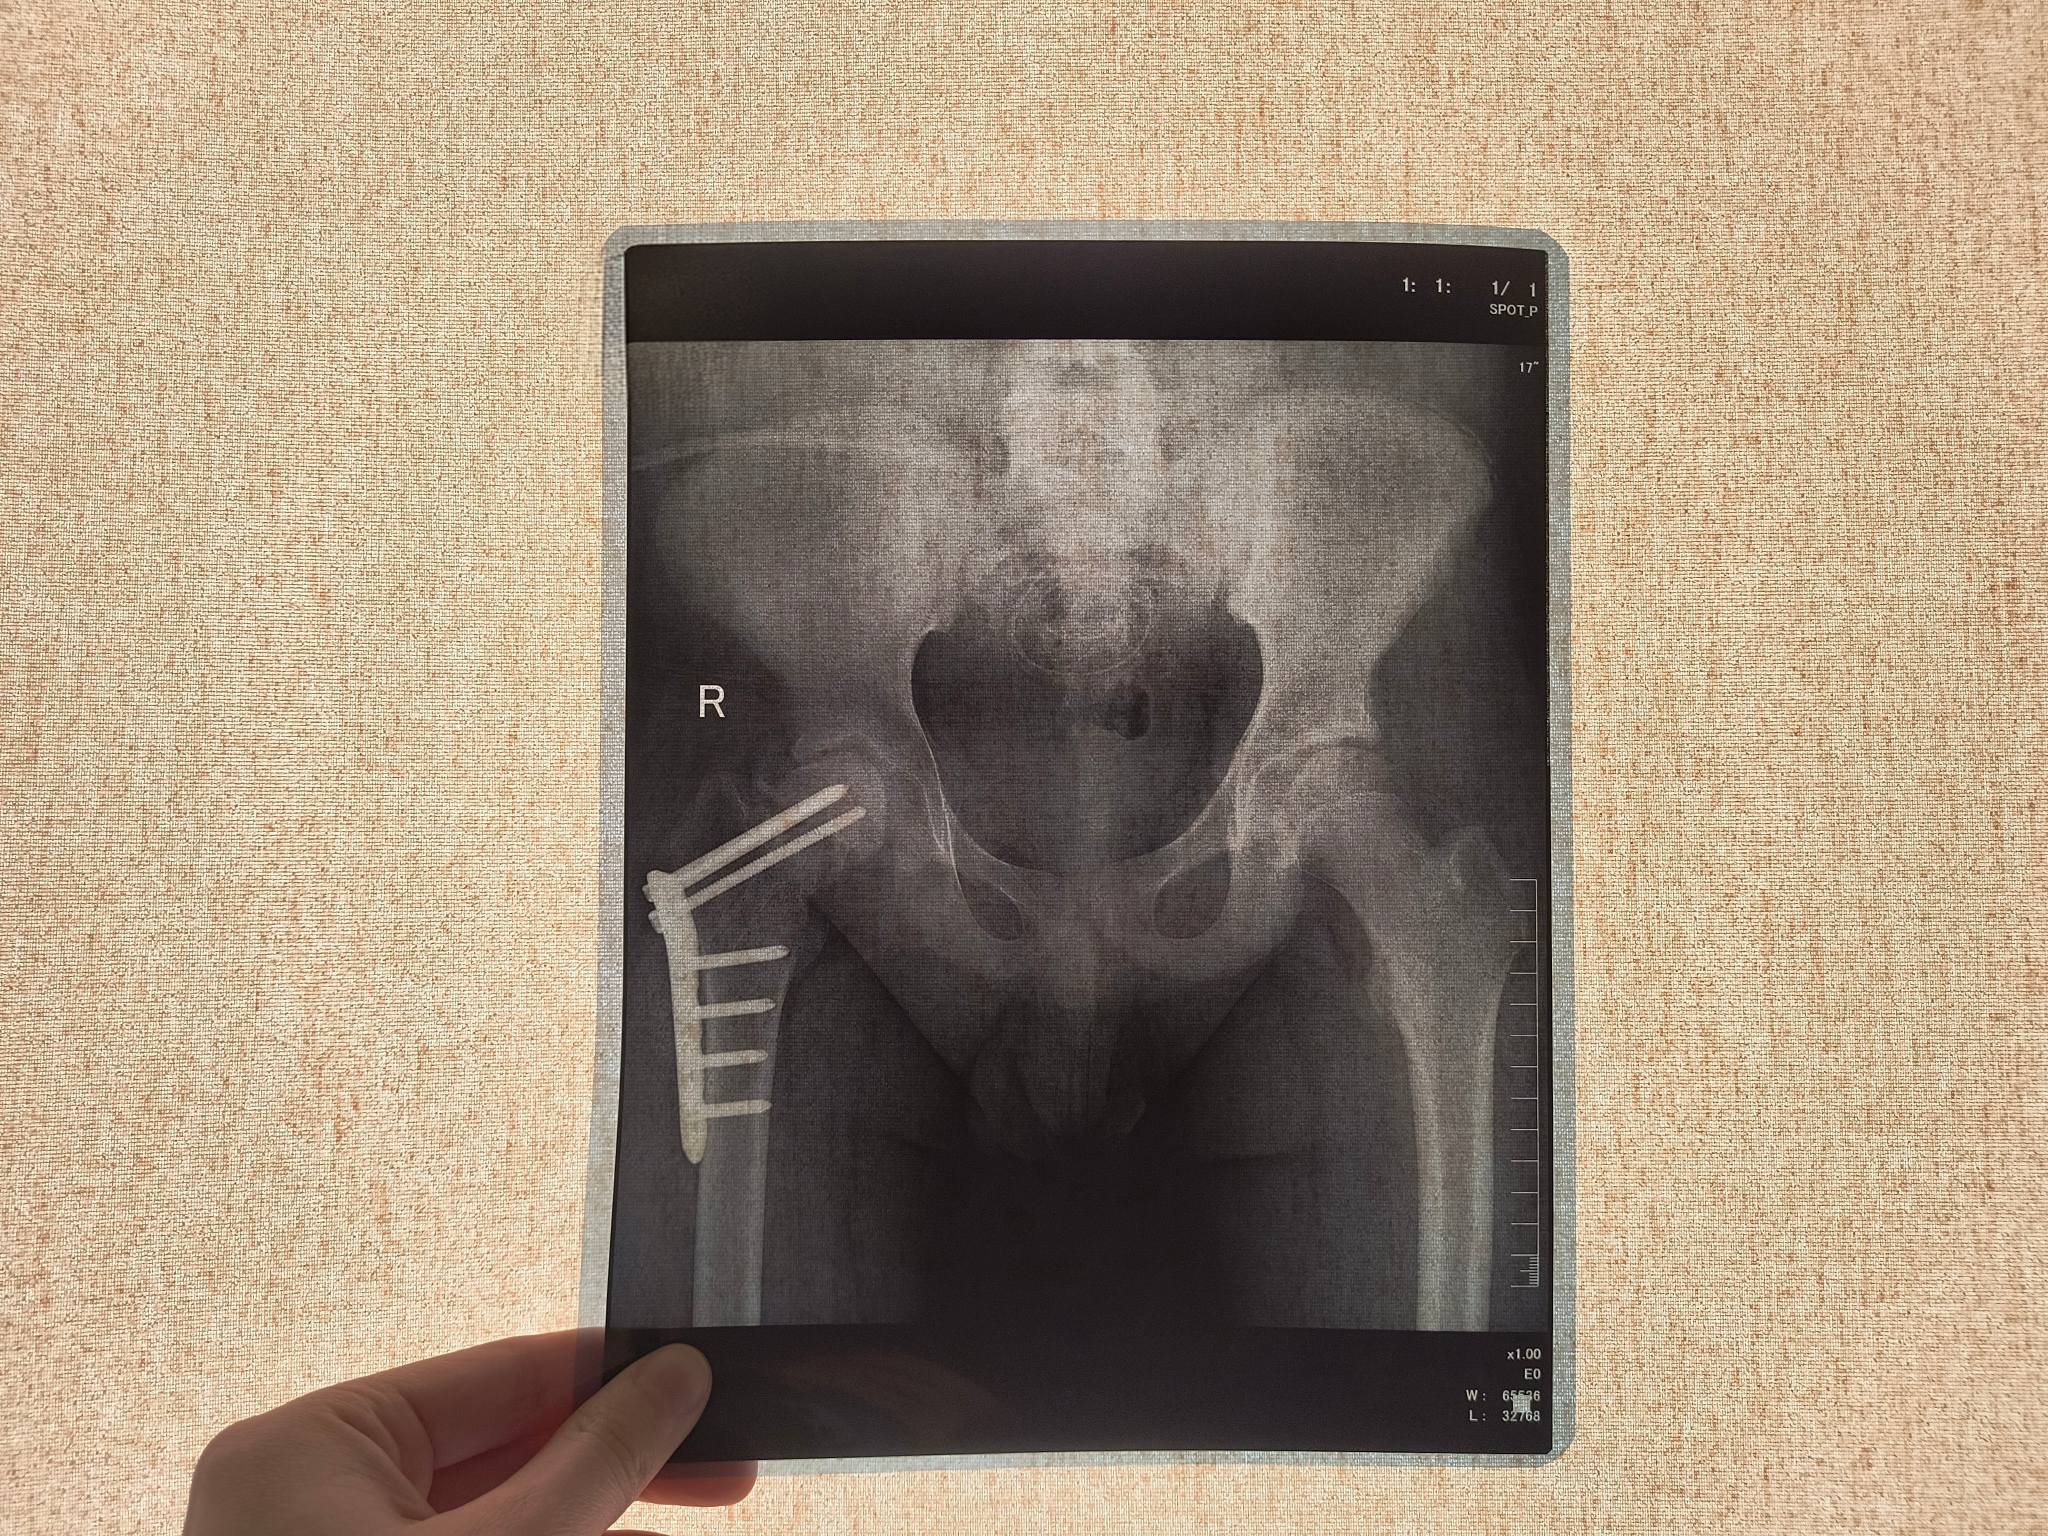

У Львові вперше в Україні підлітку зростили стегнову кістку стовбуровими клітинами. Фото: Дитяча лікарня Святого МиколаяУ Львові лікарі вперше в Україні зростили стегнову кістку 14-річному підлітку за допомогою технології введення стовбурових клітин.

У червні 2025 року у підлітка виникла нова проблема — він не зміг підвестися з ліжка. Спочатку лікарі підозрювали параліч або поліомієліт, однак обстеження показало перелом шийки стегна.

Як з’ясувалося, кістка зламалася без травми через крихкість. Аналізи показали критично високий рівень креатиніну — близько 700, що свідчило про тяжке ураження нирок і порушення мінерального обміну.

У лікарні Дніпра підлітку зафіксували перелом гвинтами. Після цього стан нирок різко погіршився, і вони повністю відмовили. Відтоді хлопець перебуває на гемодіалізі. Через слабкість кісткової тканини гвинти змістилися та почали руйнувати кульшовий суглоб.

У Львові вперше в Україні підлітку зростили стегнову кістку стовбуровими клітинами. Фото: Дитяча лікарня Святого МиколаяЗ огляду на необхідність трансплантації нирки родина звернулася до лікарів Першого медоб’єднання Львова. У Дитячій лікарні Святого Миколая пацієнта також оглянули ортопеди-травматологи та вирішили застосувати сучасну методику відновлення кістки за допомогою стовбурових клітин.

Лікарі ввели стовбурові клітини безпосередньо в місце перелому. Їх отримали з жирової тканини пацієнта. За словами медиків, ця методика стимулює утворення нових кісткових клітин і сприяє зрощенню.

У лікарні зазначають, що ця технологія є інноваційною та наразі застосовується в Україні лише в цьому медзакладі.

Після процедури минуло два тижні. Підліток уже почав ставати на ногу з опорою на ходунці. Лікарі очікують, що після повного зрощення кістки він зможе самостійно ходити.